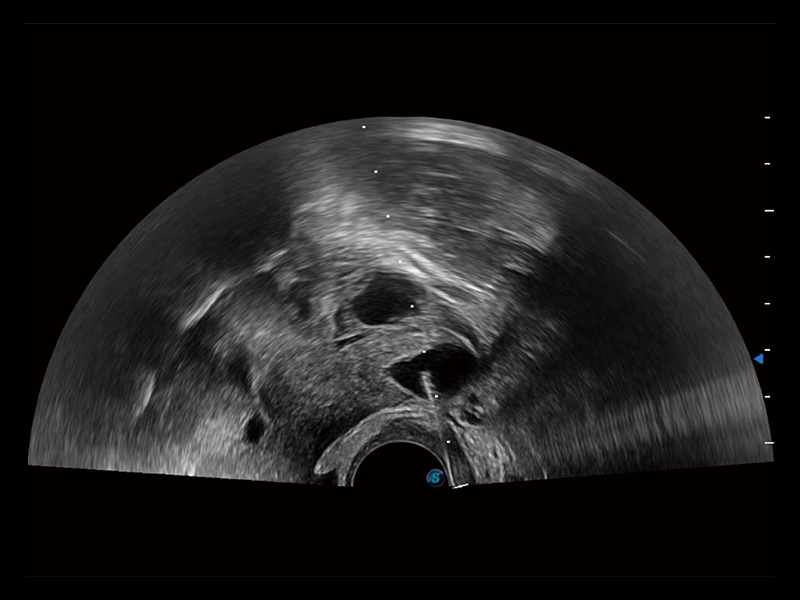

卵巢多囊样改变

中央型宫腔粘连